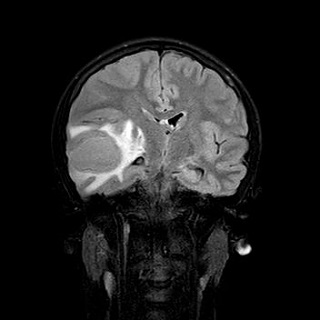

Se realiza una RM con el siguiente resultado: colección temporal derecha de aspecto polilobulado, con un eje máximo anteroposterior de aproximadamente 44 mm, que presenta marcada restricción de la difusión, así como realce parietal tras la administración de contraste. Dicha colección asocia importante edema perilesional que condiciona efecto masa sobre el sistema ventricular ipsilateral con desviación de la línea media hacia la izquierda aproximadamente 7 mm. Los hallazgos descritos son compatibles con absceso.